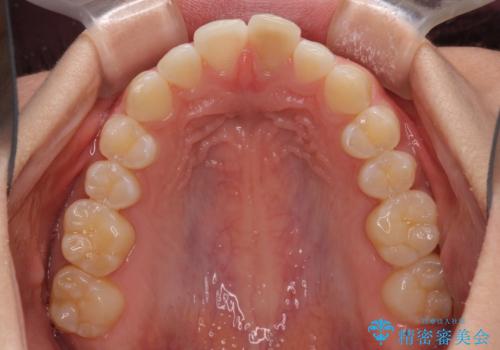

- 変色した前歯と突出した口元を気にして来院された患者様です。

口元の突出感はインビザラインにより歯列を整え、その後に、前歯をオーダーメイドタイプのオールセラミッククラウンにて補綴治療することとしました。

長時間のマウスピース装着と、患者様自身でのゴムかけに協力いただき、口元の突出感をしっかりと改善することができました。

前歯のオールセラミッククラウンもまるで本物の歯のように仕上がり、患者様には大変満足していただきました。